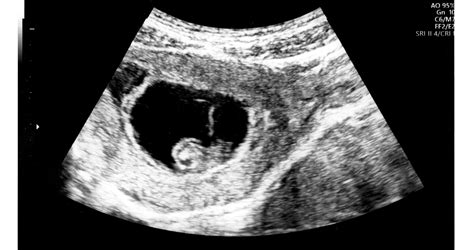

Az ultrahang vizsgálatokon mindig ellenőrzik a lepény érettségi fokát. A méhlepény érettségi fokozatai egy ultrahangos besorolást jelentenek, mely azt mutatja meg, hogyan változik a lepény szerkezete és működése a terhesség ideje alatt. Ezt a besorolást az ún. Grannum-skála alapján végzik. Az érettség értéke 0, 1, 2 vagy 3-as lehet.